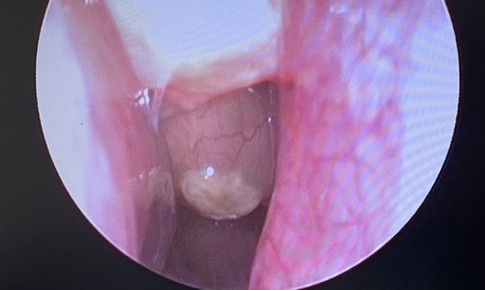

SKĐS - Vừa viêm mũi xoang mạn tính, polyp mũi độ III, lại thêm hàng loạt bệnh lý nền như tăng huyết áp, bệnh tim mạch… người đàn ông 57 tuổi được các y bác sĩ Bệnh viện E phẫu thuật, cứu khỏi tình trạng nghẹt mũi kéo dài, ảnh hưởng đến sinh hoạt.